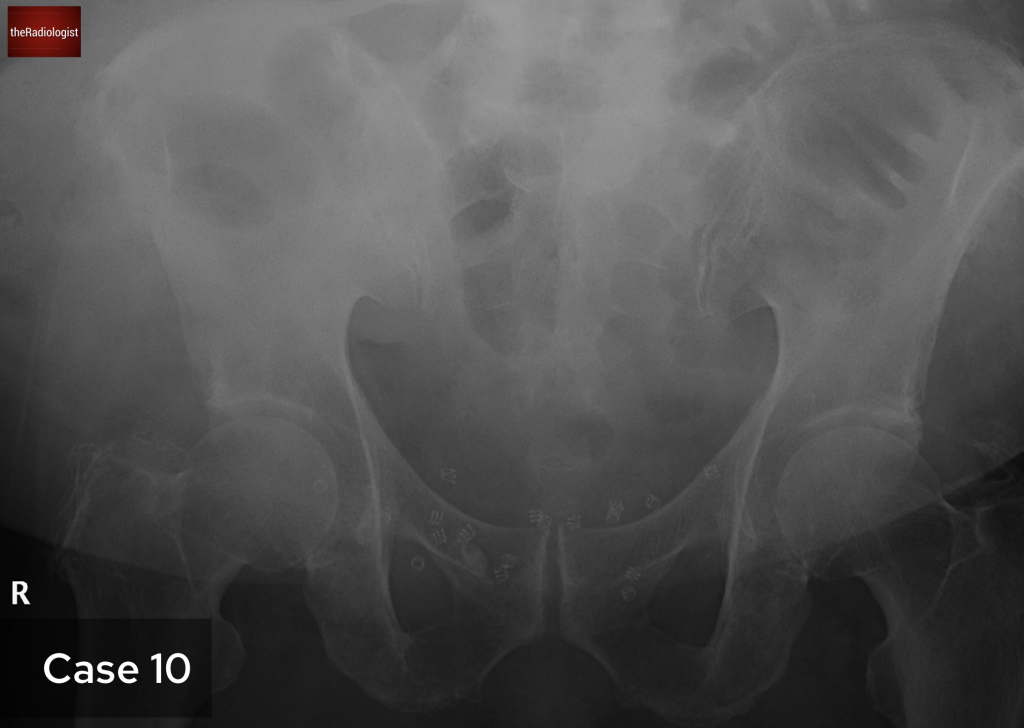

On a follow up MRI scan 2 months later we can see the right psoas is now returning to normal.

The patient was treated with a long course of antibiotics and we saw a good response on imaging with improvement in the right psoas abnormality at 2 months.